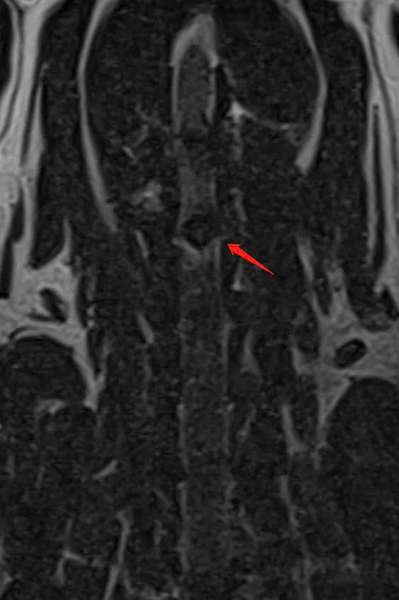

Chẩn đoán hình ảnh

- X-quang: Phát hiện hẹp khoảng cách đốt sống C3 – C4.

X-quang cổ cho thấy khoảng cách giữa đốt sống C3 – C4 bị thu hẹp, gợi ý đĩa đệm cổ thoát vị.

X-quang cổ cho thấy khoảng cách giữa đốt sống cổ C3 và C4 bị thu hẹp, gợi ý đĩa đệm cổ bị thoát vị. Hình ảnh X-quang bên cho thấy đĩa đệm bị đẩy từ phía bụng ra sau, đây là thông tin quan trọng cho quá trình phẫu thuật loại bỏ đĩa đệm.